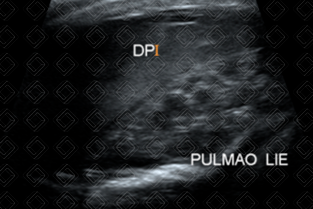

Texto alternativo para a imagem Figura 4. Créditos: Dra. Elazir Mota - Rio de Janeiro/RJ

Texto alternativo para a imagem Figura 5. Créditos: Dra. Elazir Mota - Rio de Janeiro/RJ

Descrição das figuras 4 e 5: Caso 2: Ultrassonografia de tórax evidencia um volumoso derrame pleural esquerdo com atelectasia compressiva do parênquima pulmonar desse lado.